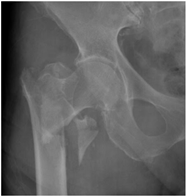

For X-ray 2, four scenarios were developed.![]() | Scenario 1: What would be your operation preference for a mobile patient aged 50–70 and with an ASA score of 1–2? Scenario 2: What would be your operation preference for a mobile patient aged 71 years or older with an ASA score of 1–2? Scenario 3: What would be your operation preference for a mobile patient aged 50–70 with an ASA score of 3–4? Scenario 4: What would be your operation preference for a mobile patient aged 71 years or older with an ASA score of 3–4? |